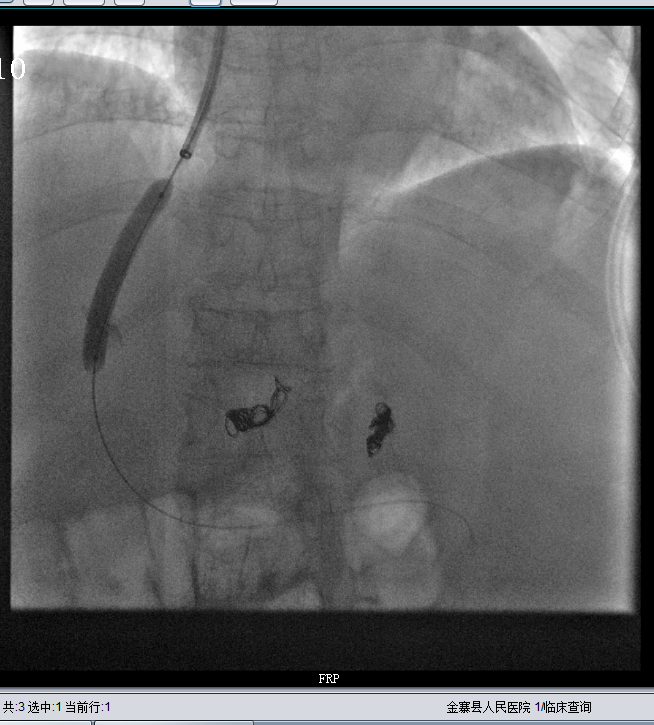

扩张肝静脉门静脉分流道

肝静脉门静脉分流道通畅